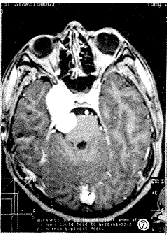

图4 右侧三叉神经鞘瘤。横轴位T1加权像显示肿瘤呈哑铃形骑跨于中后颅窝,呈混杂等或稍低信号,第四脑室受压变形,右岩骨尖骨质吸收。

图5 同图4病例,横轴位T2加权像显示肿瘤呈较均匀高信号。

图6 同图4病例,注射Gd-DTPA后横轴位T1加权像显示肿瘤实性部分呈均匀强化,囊性部分呈环状强化。

6例中5例为单发病灶,1例为多发病灶。其中左侧3例、右侧4例,共7个肿瘤。肿瘤最大为6.4cm×3.1cm×3.0cm,最小为2.8cm×1.5cm×1.0cm。MR检查示5例单发肿瘤呈哑铃状骑跨于中后颅窝之间(图1、2),1例除见骑跨征象外,其另1病灶呈卵圆形位于中颅窝。肿瘤有5个发生囊变,且4个较大的囊腔均位于后颅窝,而2例并发神经纤维瘤病者基本为实性,仅一个肿瘤在中后颅窝均有多个小囊腔(图3、4)。位于中颅窝的肿瘤边界都清楚,周边见完整肿瘤包膜,多呈等或混杂T1长T2信号。而位于后颅窝的肿瘤边界清楚,但大部分无肿瘤包膜,呈长T1长T2信号。注射Gd-DTPA后扫描,肿瘤实体部分均匀强化,囊性部分呈环状、结节状强化(图5、6)。位于中颅窝半月节的肿瘤均累及海绵窦、Meckl氏腔(图7、8),同时还对颞叶深部的海马回等产生压迫。位于神经根的肿瘤对小脑、脑干、桥小脑角池及第四脑室产生压迫,引起相应的MRI表现。